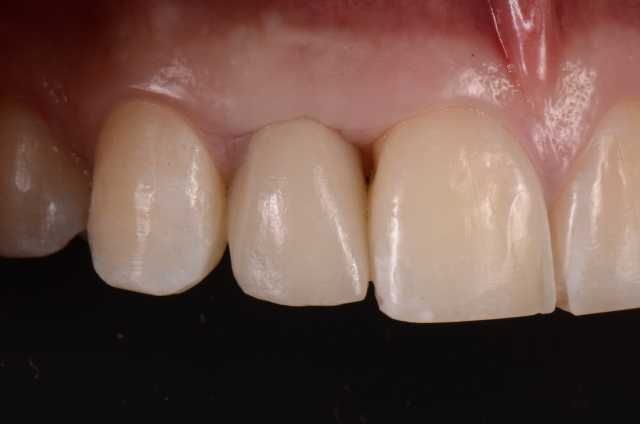

Single-tooth implants in the esthetic zone usually require a provisional restoration. The fabrication of a single-tooth implant-supported restoration requires a careful step-by-step approach to deliver a restoration that will assist the process of soft-tissue sculpting.

Here is a multi-step process showing the fabrication sequence of a screw-retained single-tooth implant provisional restoration of a lateral incisor.